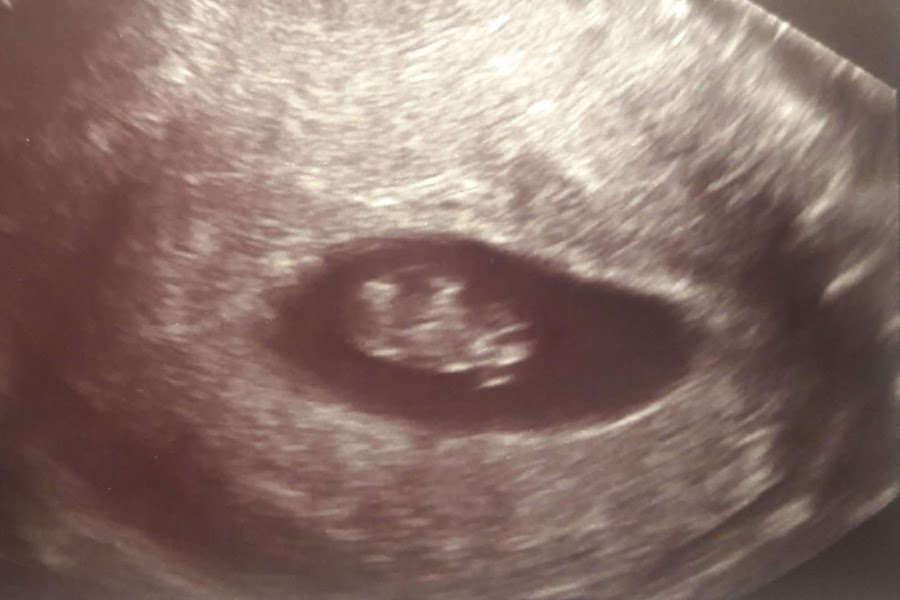

Ecografía de la semana 12

En cuanto a las pruebas que me he hecho han sido varias ecografías y un primer análisis donde salió baja la vitamina D, aunque la más importante es la de la semana 12, en la que ven el pliegue nucal, donde junto a un análisis de sangre (cribado) descartan posibles problemas cromosómicos (el 21 y el 18); yo tenía un poco de miedo por mi edad (este año cumplo 37), pero me salió un riesgo bastante bajo, por lo que se descartó realizar la anmiocentesis.